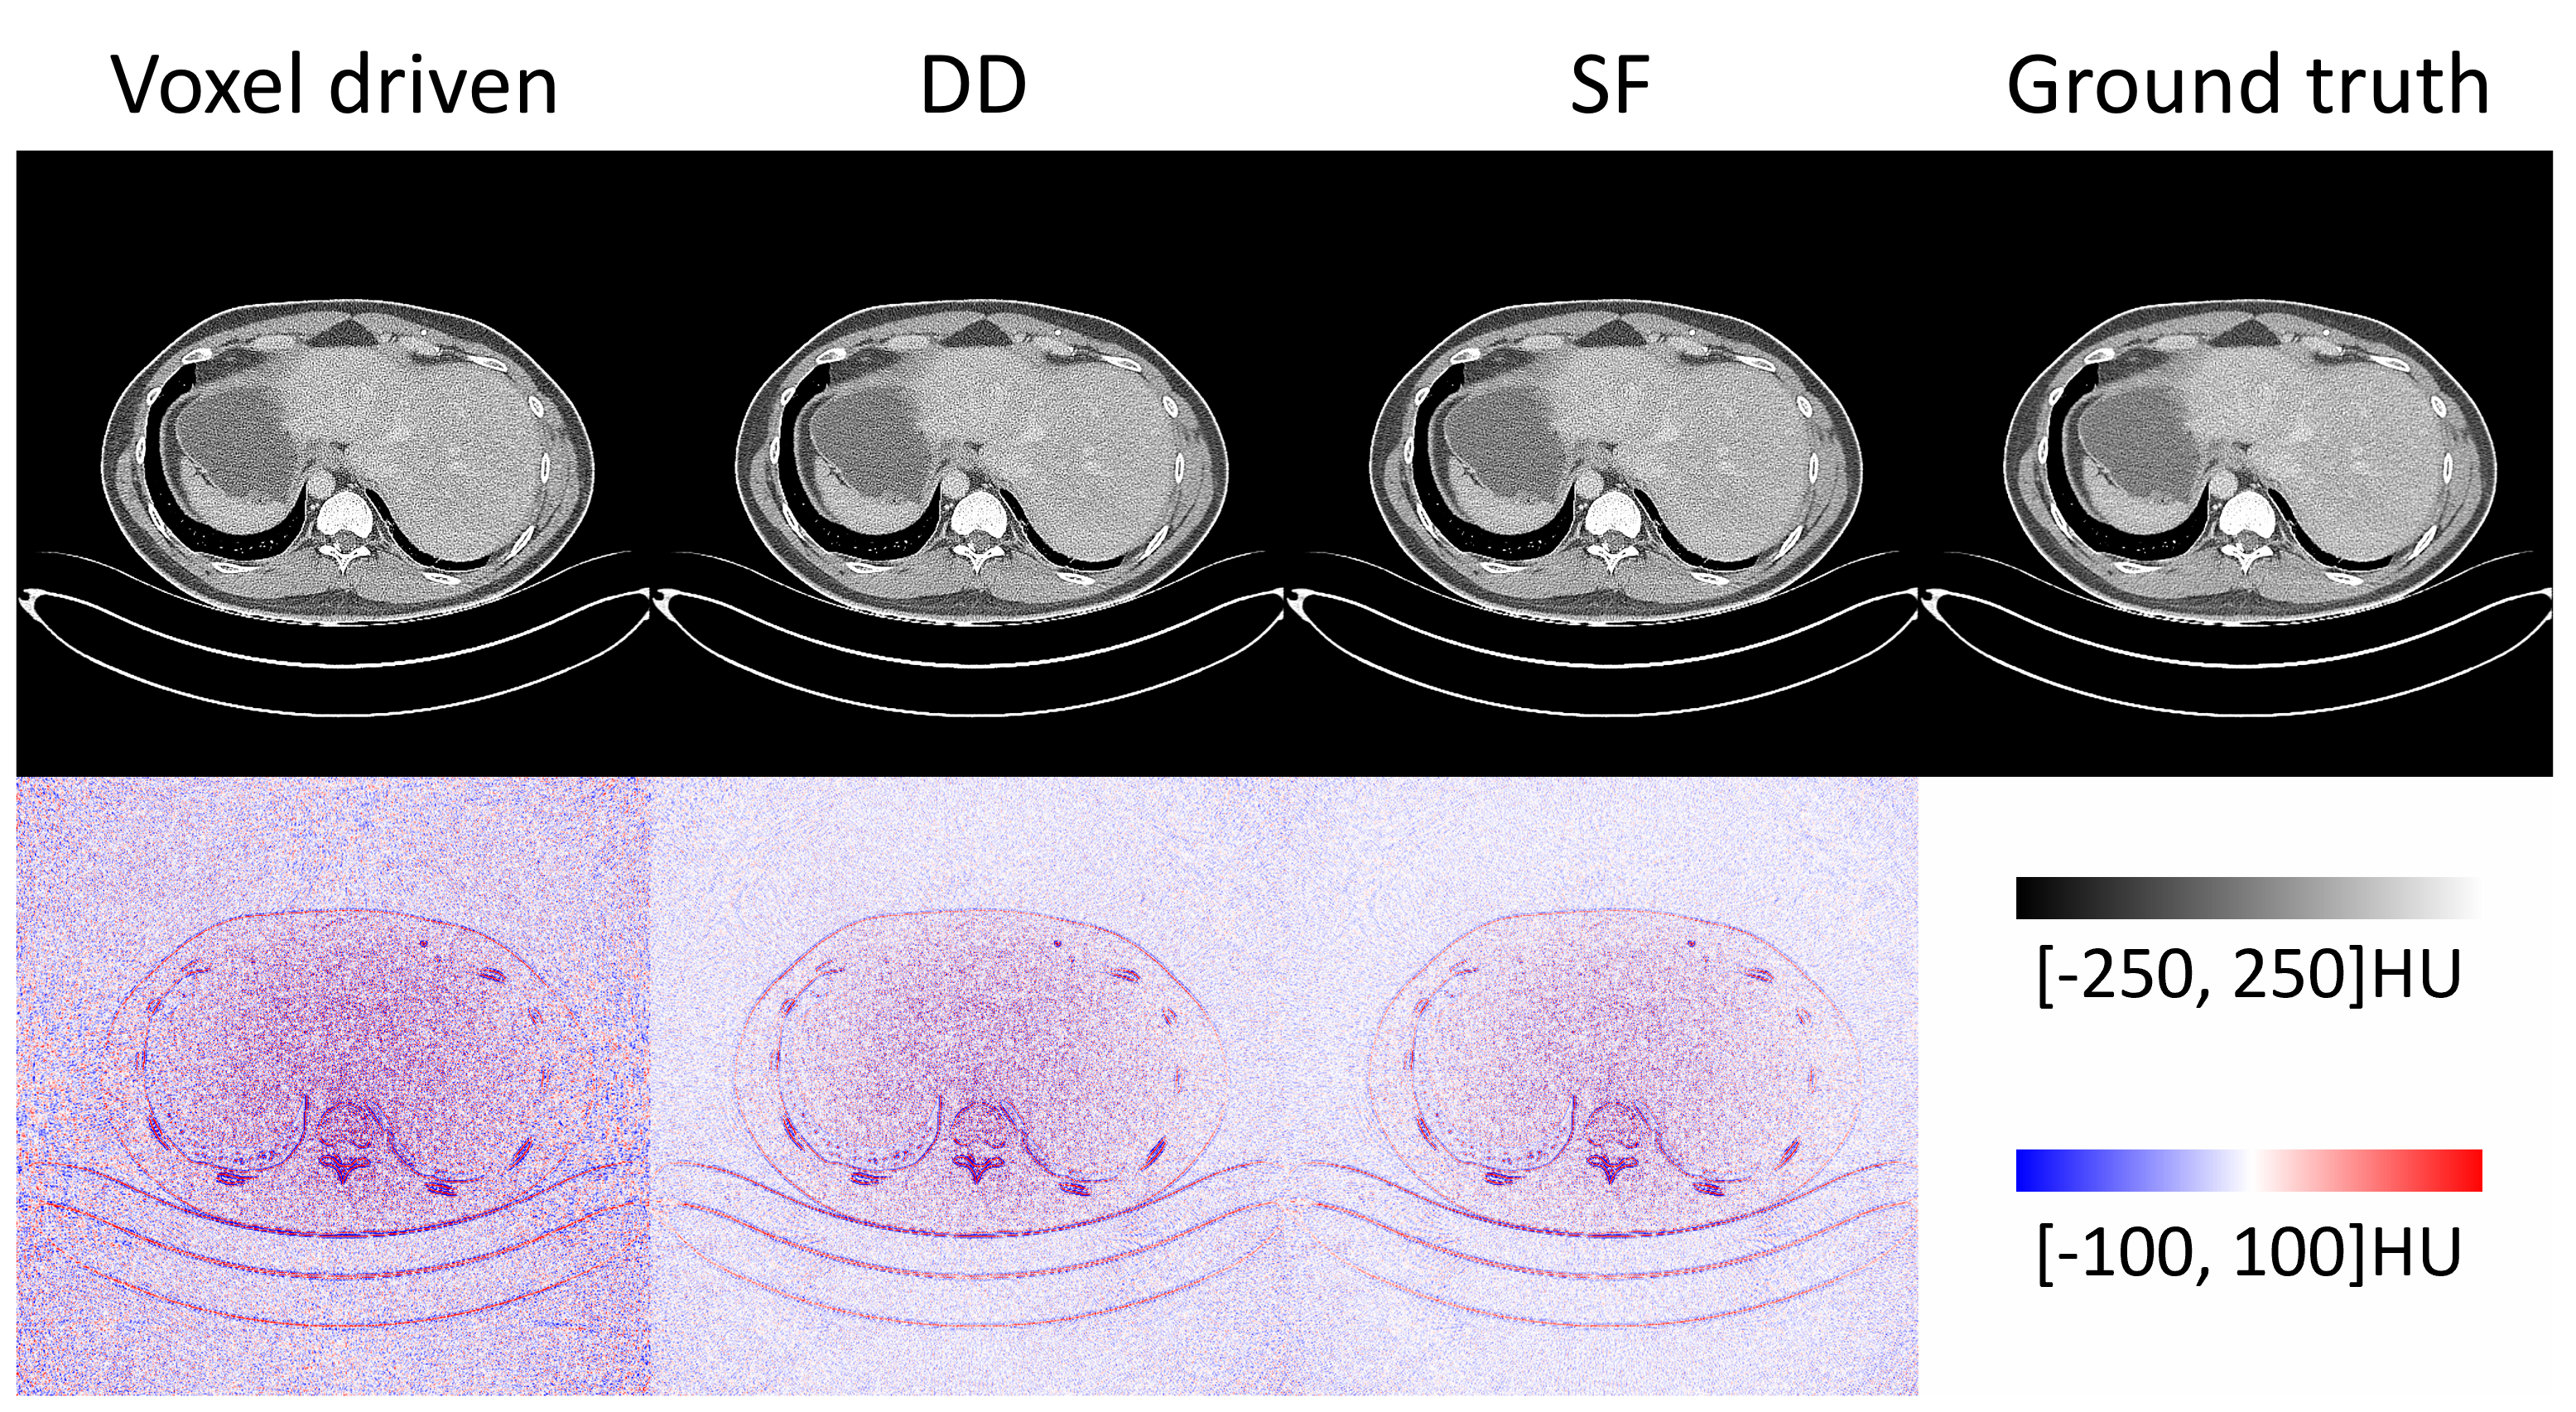

Next, we validate the CTorch projector for a curved detector using public sinogram data from the AAPM MAR challenge[AAPM_CT_MAR_Challenge]. This dataset simulates 1D projections acquired using a curved detector with a 1.25-pixel lateral offset. The reconstruction results are summarized in Fig. 7. The reconstructed images obtained with different projectors closely match the ground truth. The corresponding error maps further illustrate that no significant geometric distortions are present in the reconstruction, with errors primarily concentrated around sharp edges. These errors may be attributed to differences in the applied filtering function.

Figure 6: FBP reconstruction using the curved-detector projections from AAPM MAR challenge dataset. The bottom row display the difference images between CTorch reconstruction and the ground truth.